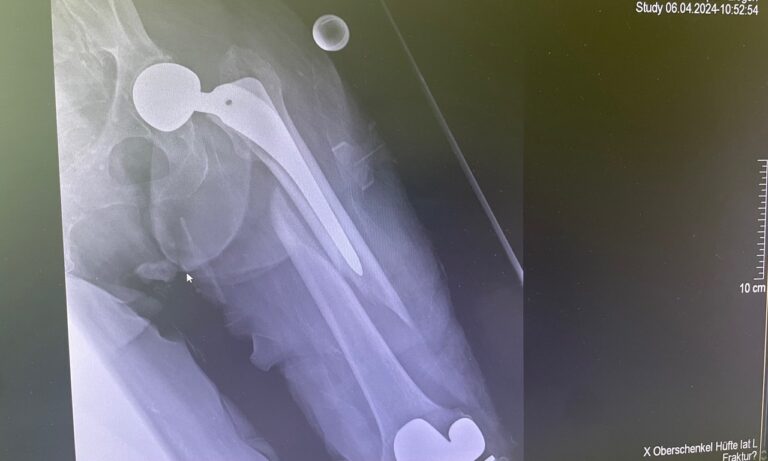

- Κάταγμα μηριαίου αυχένα (πολύ συχνό στους ηλικιωμένους)

- Διαφυσιακά κατάγματα μηριαίου ή κνήμης

Διάγνωση

- Ακτινογραφία

- Αξονική τομογραφία (CT) σε σύνθετα κατάγματα

- Χειρουργική αποκατάσταση (πλάκες, βίδες, ενδομυελικοί ήλοι)